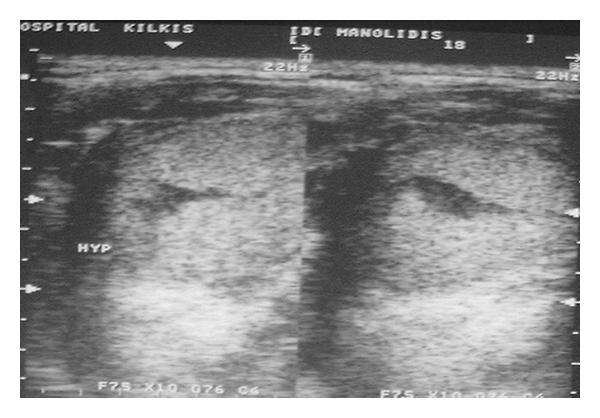

Dermoid cysts in the floor of the mouth may be congenital or acquired. The congenital form, according to the main theory, originates from embryonic cells of the 1st and 2nd branchial arch. The acquired form may be due to traumatic or iatrogenic causes and as a result of the occlusion of a sebaceous gland duct. Its occurrence is less and is estimated to be from 1.6 to 6.4% of the dermoid cysts of the body in adults and 0.29% of the head and neck tumors occurring in children. They may also be classified as anatomical and histological. Anatomically, they are divided into median genioglossal, median geniohyoid, and lateral cysts, while histologically they are divided into epidermoid, dermoid cysts and teratomas. Clinically, a distinction between supra and inferior type as well as between central and lateral type is proposed in relation to themylohyoidmuscle and themidline, respectively. Histologically, an estimation of dermoid, epidermoid, and teratoid cysts is reported. Enucleation via intraoral and/or extraoral approach is the method of treatment. Two case reports of dermoid cysts in the floor of the mouth are presented in this paper, and an evaluation with regard to pathology, clinical findings, differential diagnosis, and treatment is discussed.

口腔底部的皮样囊肿可能是先天性的或后天获得性的。根据主要理论,先天性皮样囊肿起源于第一和第二鳃弓的胚胎细胞。后天获得性皮样囊肿可能是由创伤或医源性原因引起的,也可能是皮脂腺导管阻塞的结果。其发生率较低,据估计,在成人体表皮样囊肿中占1.6%至6.4%,在儿童头颈部肿瘤中占0.29%。它们也可按解剖学和组织学进行分类。在解剖学上,它们分为正中颏舌肌型、正中颏舌骨型和外侧囊肿型,而在组织学上,它们分为表皮样囊肿、皮样囊肿和畸胎瘤。临床上,分别根据下颌舌骨肌和中线提出了上型和下型以及中央型和外侧型的区分。在组织学上,报告了皮样囊肿、表皮样囊肿和畸胎样囊肿的评估情况。通过口内和/或口外入路摘除是治疗方法。本文介绍了两例口腔底部皮样囊肿的病例报告,并讨论了病理学、临床发现、鉴别诊断和治疗方面的评估情况。